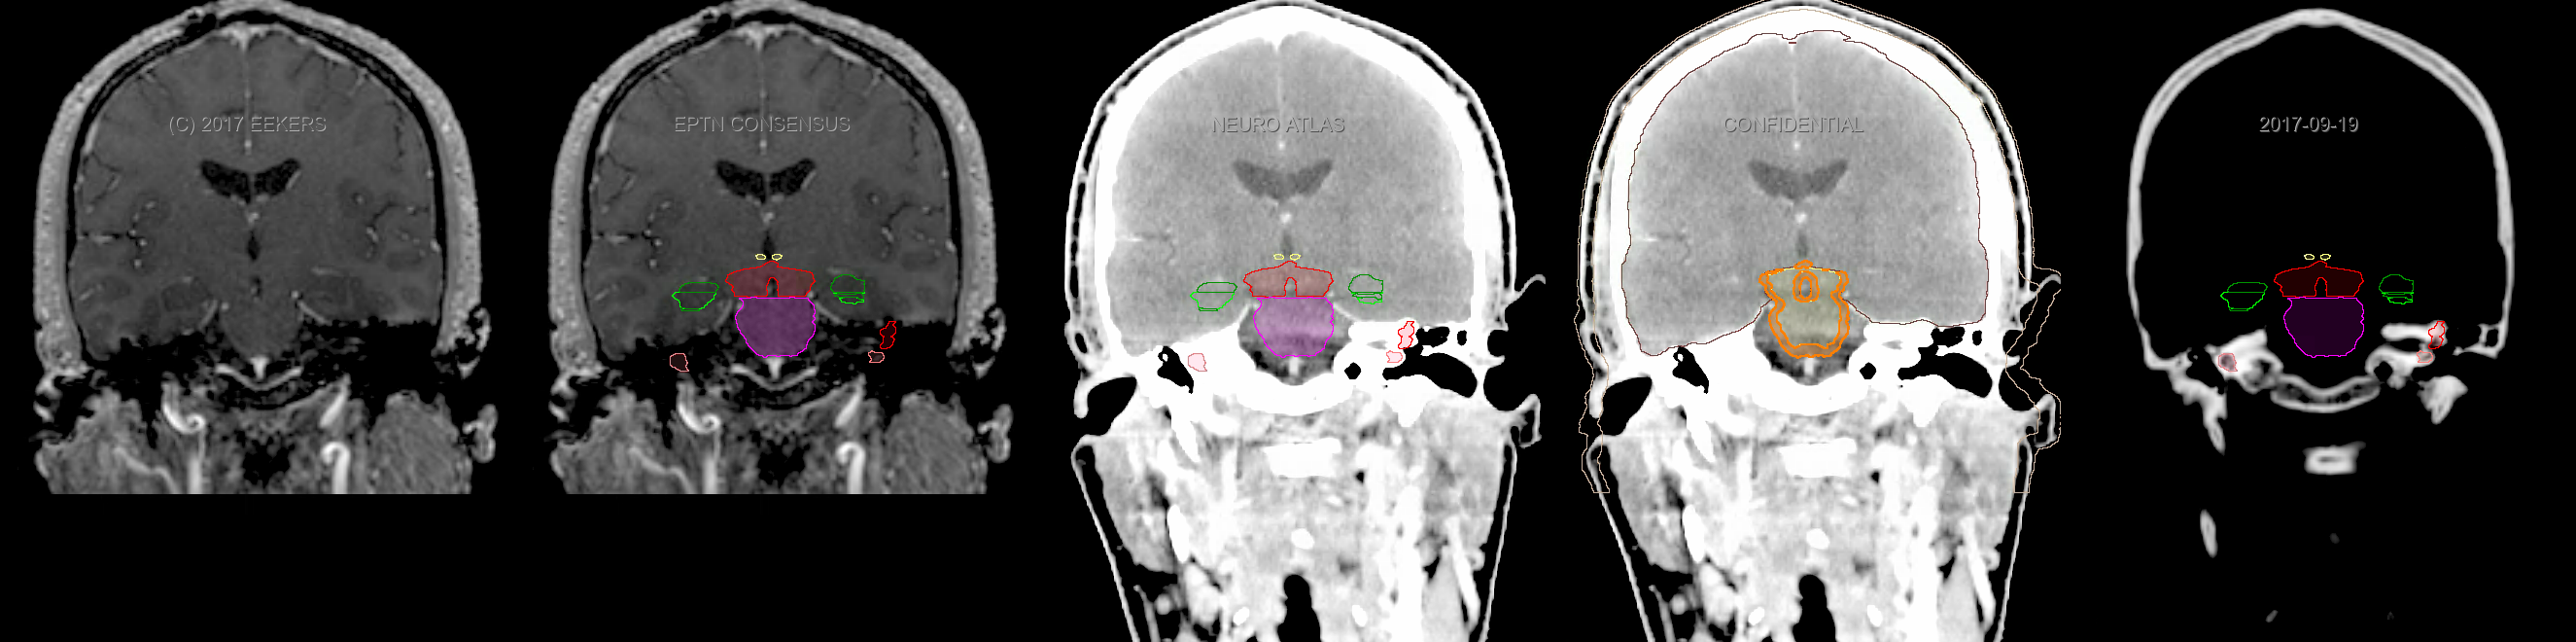

Eekers et al. have published an international neurological atlas for contouring of organs at risk in consensus with the European Particle Therapy Network (EPTN). The purpose of this consensus atlas is to decrease inter- and intra-observer variability in delineating OARs relevant for neuro-oncology. We propose this atlas is used in photon and particle therapy in order to derive consistent dosimetric data. When required this atlas will be updated according to new insights.

Included are all OARs known to be relevant for radiation-induced toxicity in neuro-oncology: brain, brainstem, cochlea, vestibulum & semicircular canals, cornea, lens, retina, lacrimal gland, optic nerve, chiasm, pituitary, hippocampus and skin. A new OAR relevant for neuro-cognition, the posterior cerebellum is also included.

Three-dimensional delineation of the fifteen consensus OARs for neuro-oncology are shown on CT and 3 Tesla (3T) MR images (slice thickness 1 mm with intravenous contrast agent). All are presented in transversal, sagittal and coronal view.

From left to right: MR without structures, MR with structures, CT (WW/WL 120/40) with structures, CT (WW/WL 120/40) with Brain and Brainstem Surface, CT (WW/WL 1500/120)with structures